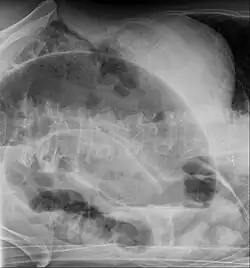

-

Coffee bean sign in a person with sigmoid volvulus -